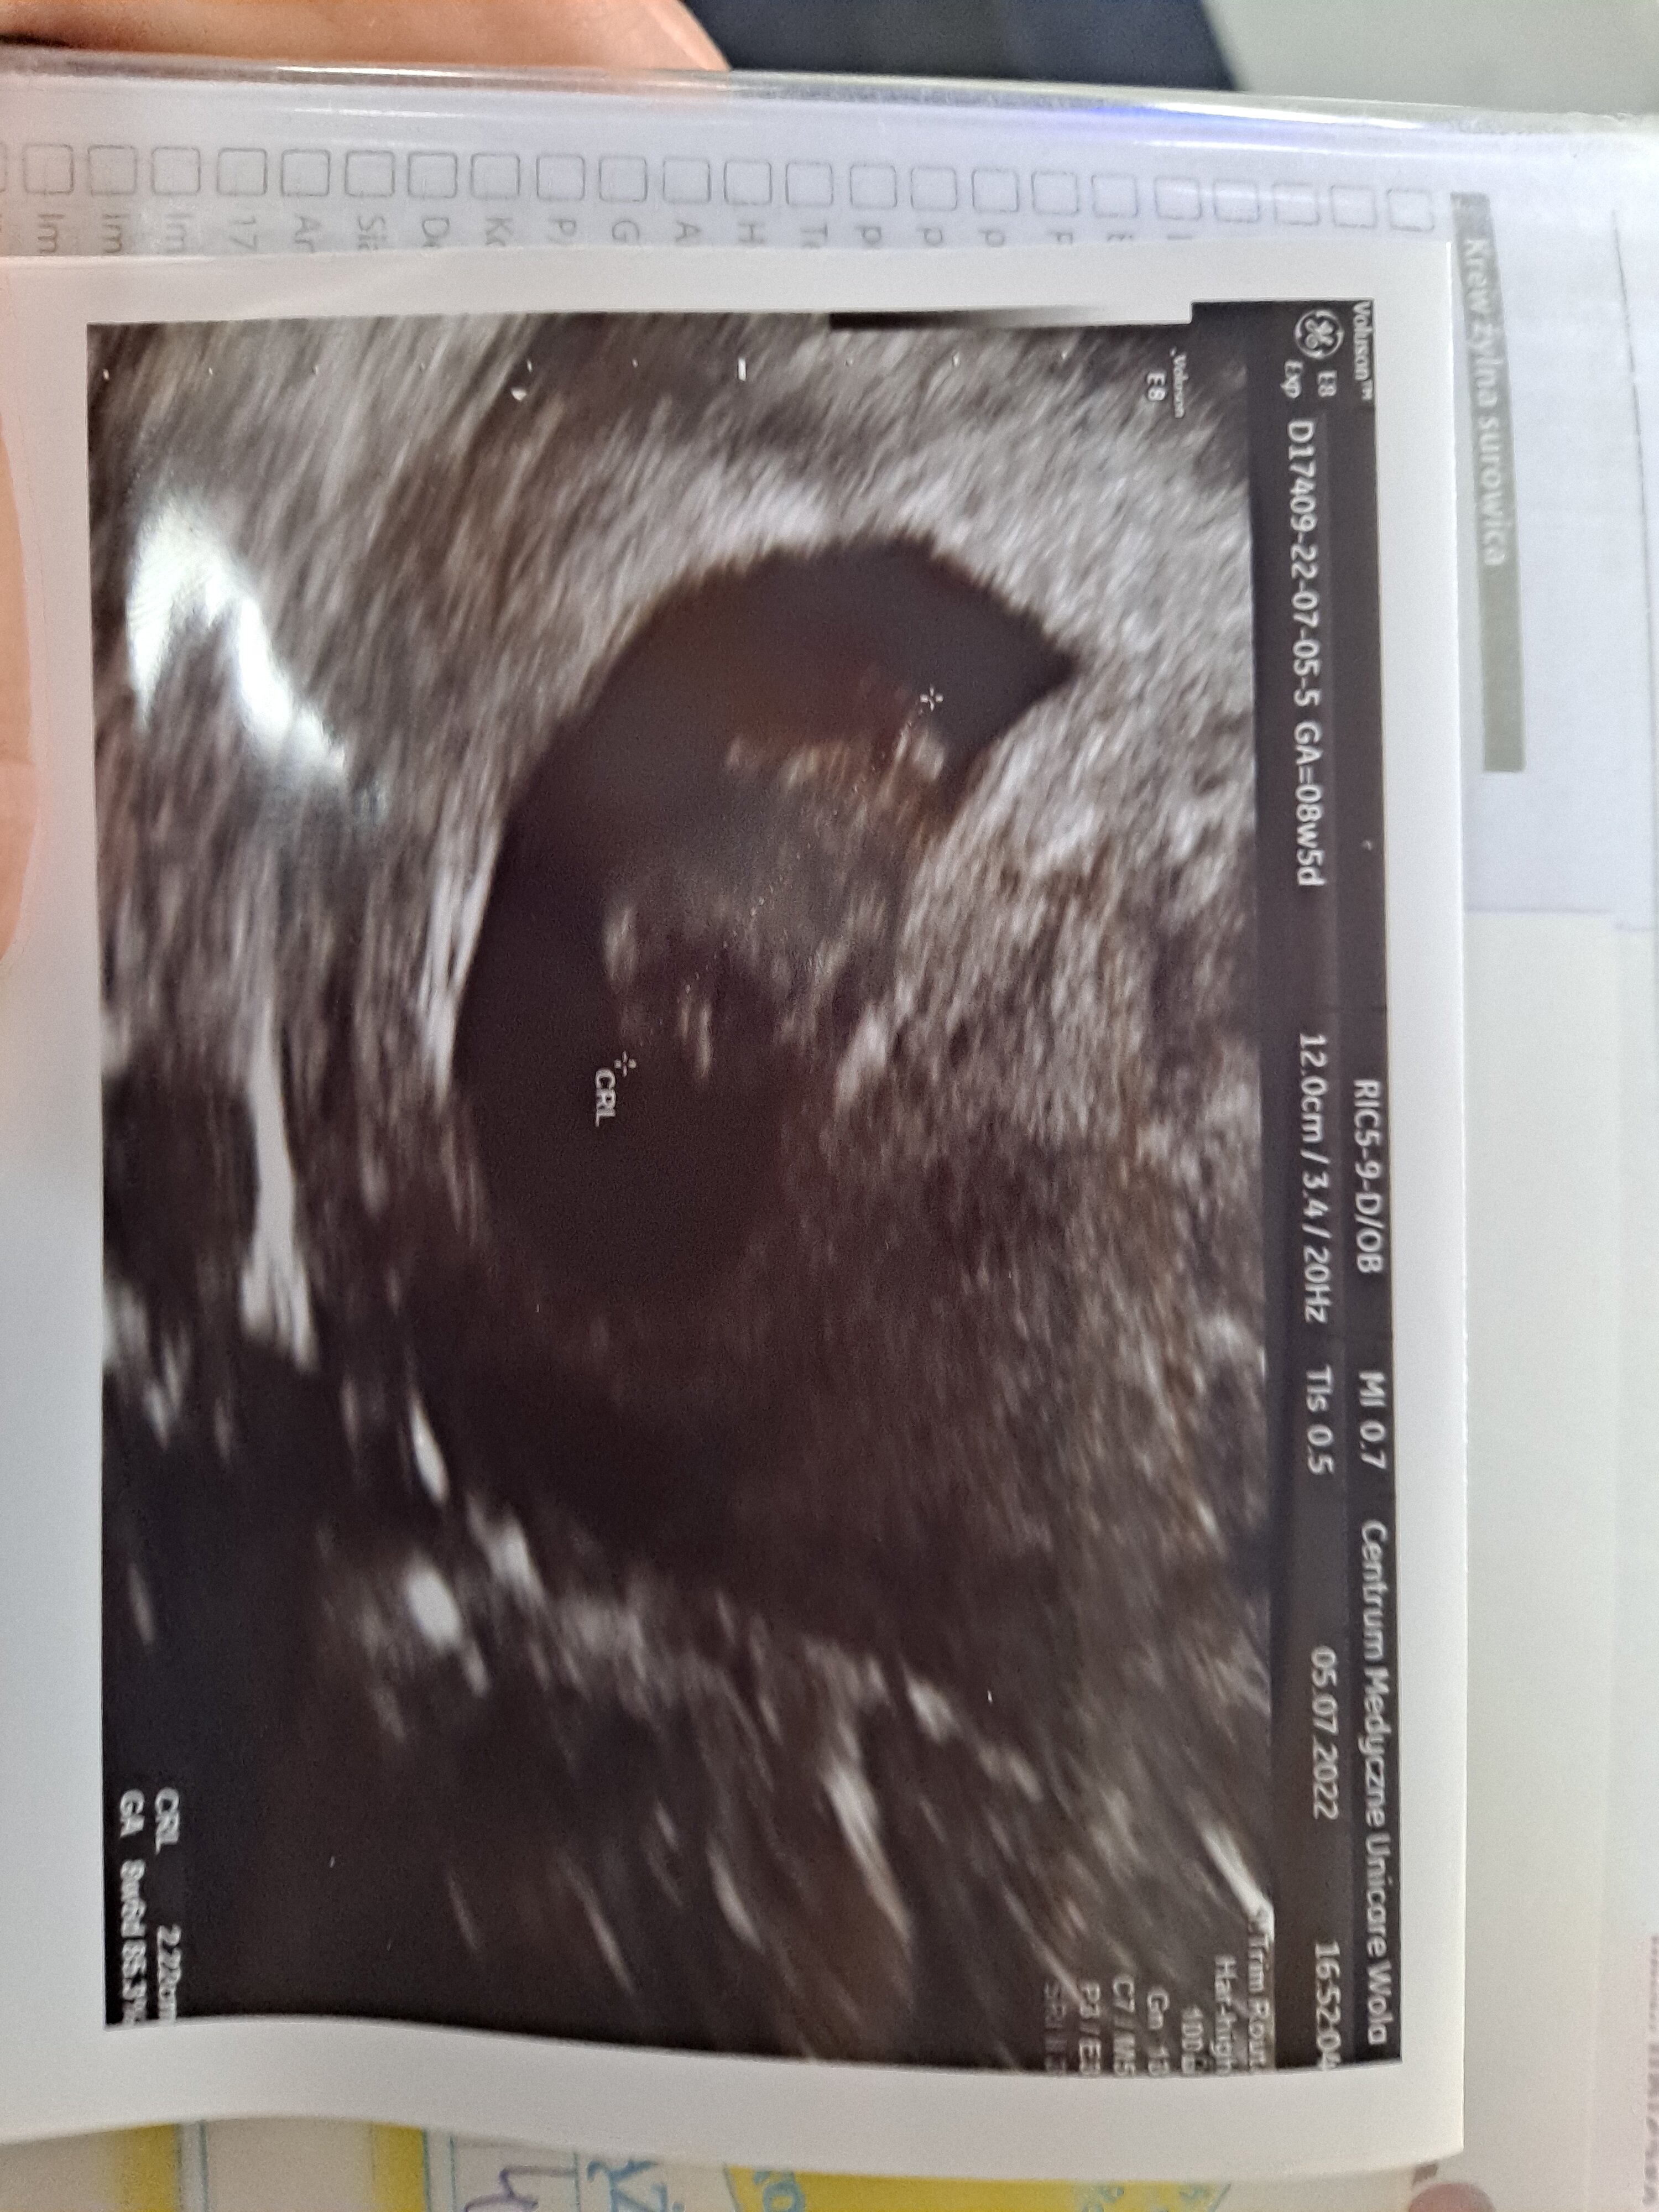

To ja się dzisiaj pochwalę zdjęciem z usg

Mdłości mi praktycznie odeszły, więc się zamartwiałam. Wg poprzedniego usg powinno być 7+2, a tutaj niespodzianka, 8+2 i serduszko bije

byłam u innego lekarza, z lepszym sprzętem. Mój prowadzący jest stary i ślepy i chyba jednak sprzęt ma słaby

teraz w końcu terminy mi się zgadzają, a nie ciąża młodsza z każdym usg

Ja po wizycie

Wszystko jest idealne jak to powiedział mój doktor.

Zbadał i na fotelu i zrobił usg.

Mój groszek mierzy 2,22mm

bije jak szalone 160 uderzeń

Obecnie mamy 8+5 tc

Termin na 9.02.2023

Jestem spokojna i szczęśliwa

ROŚNIJ MÓJ GROSZKU